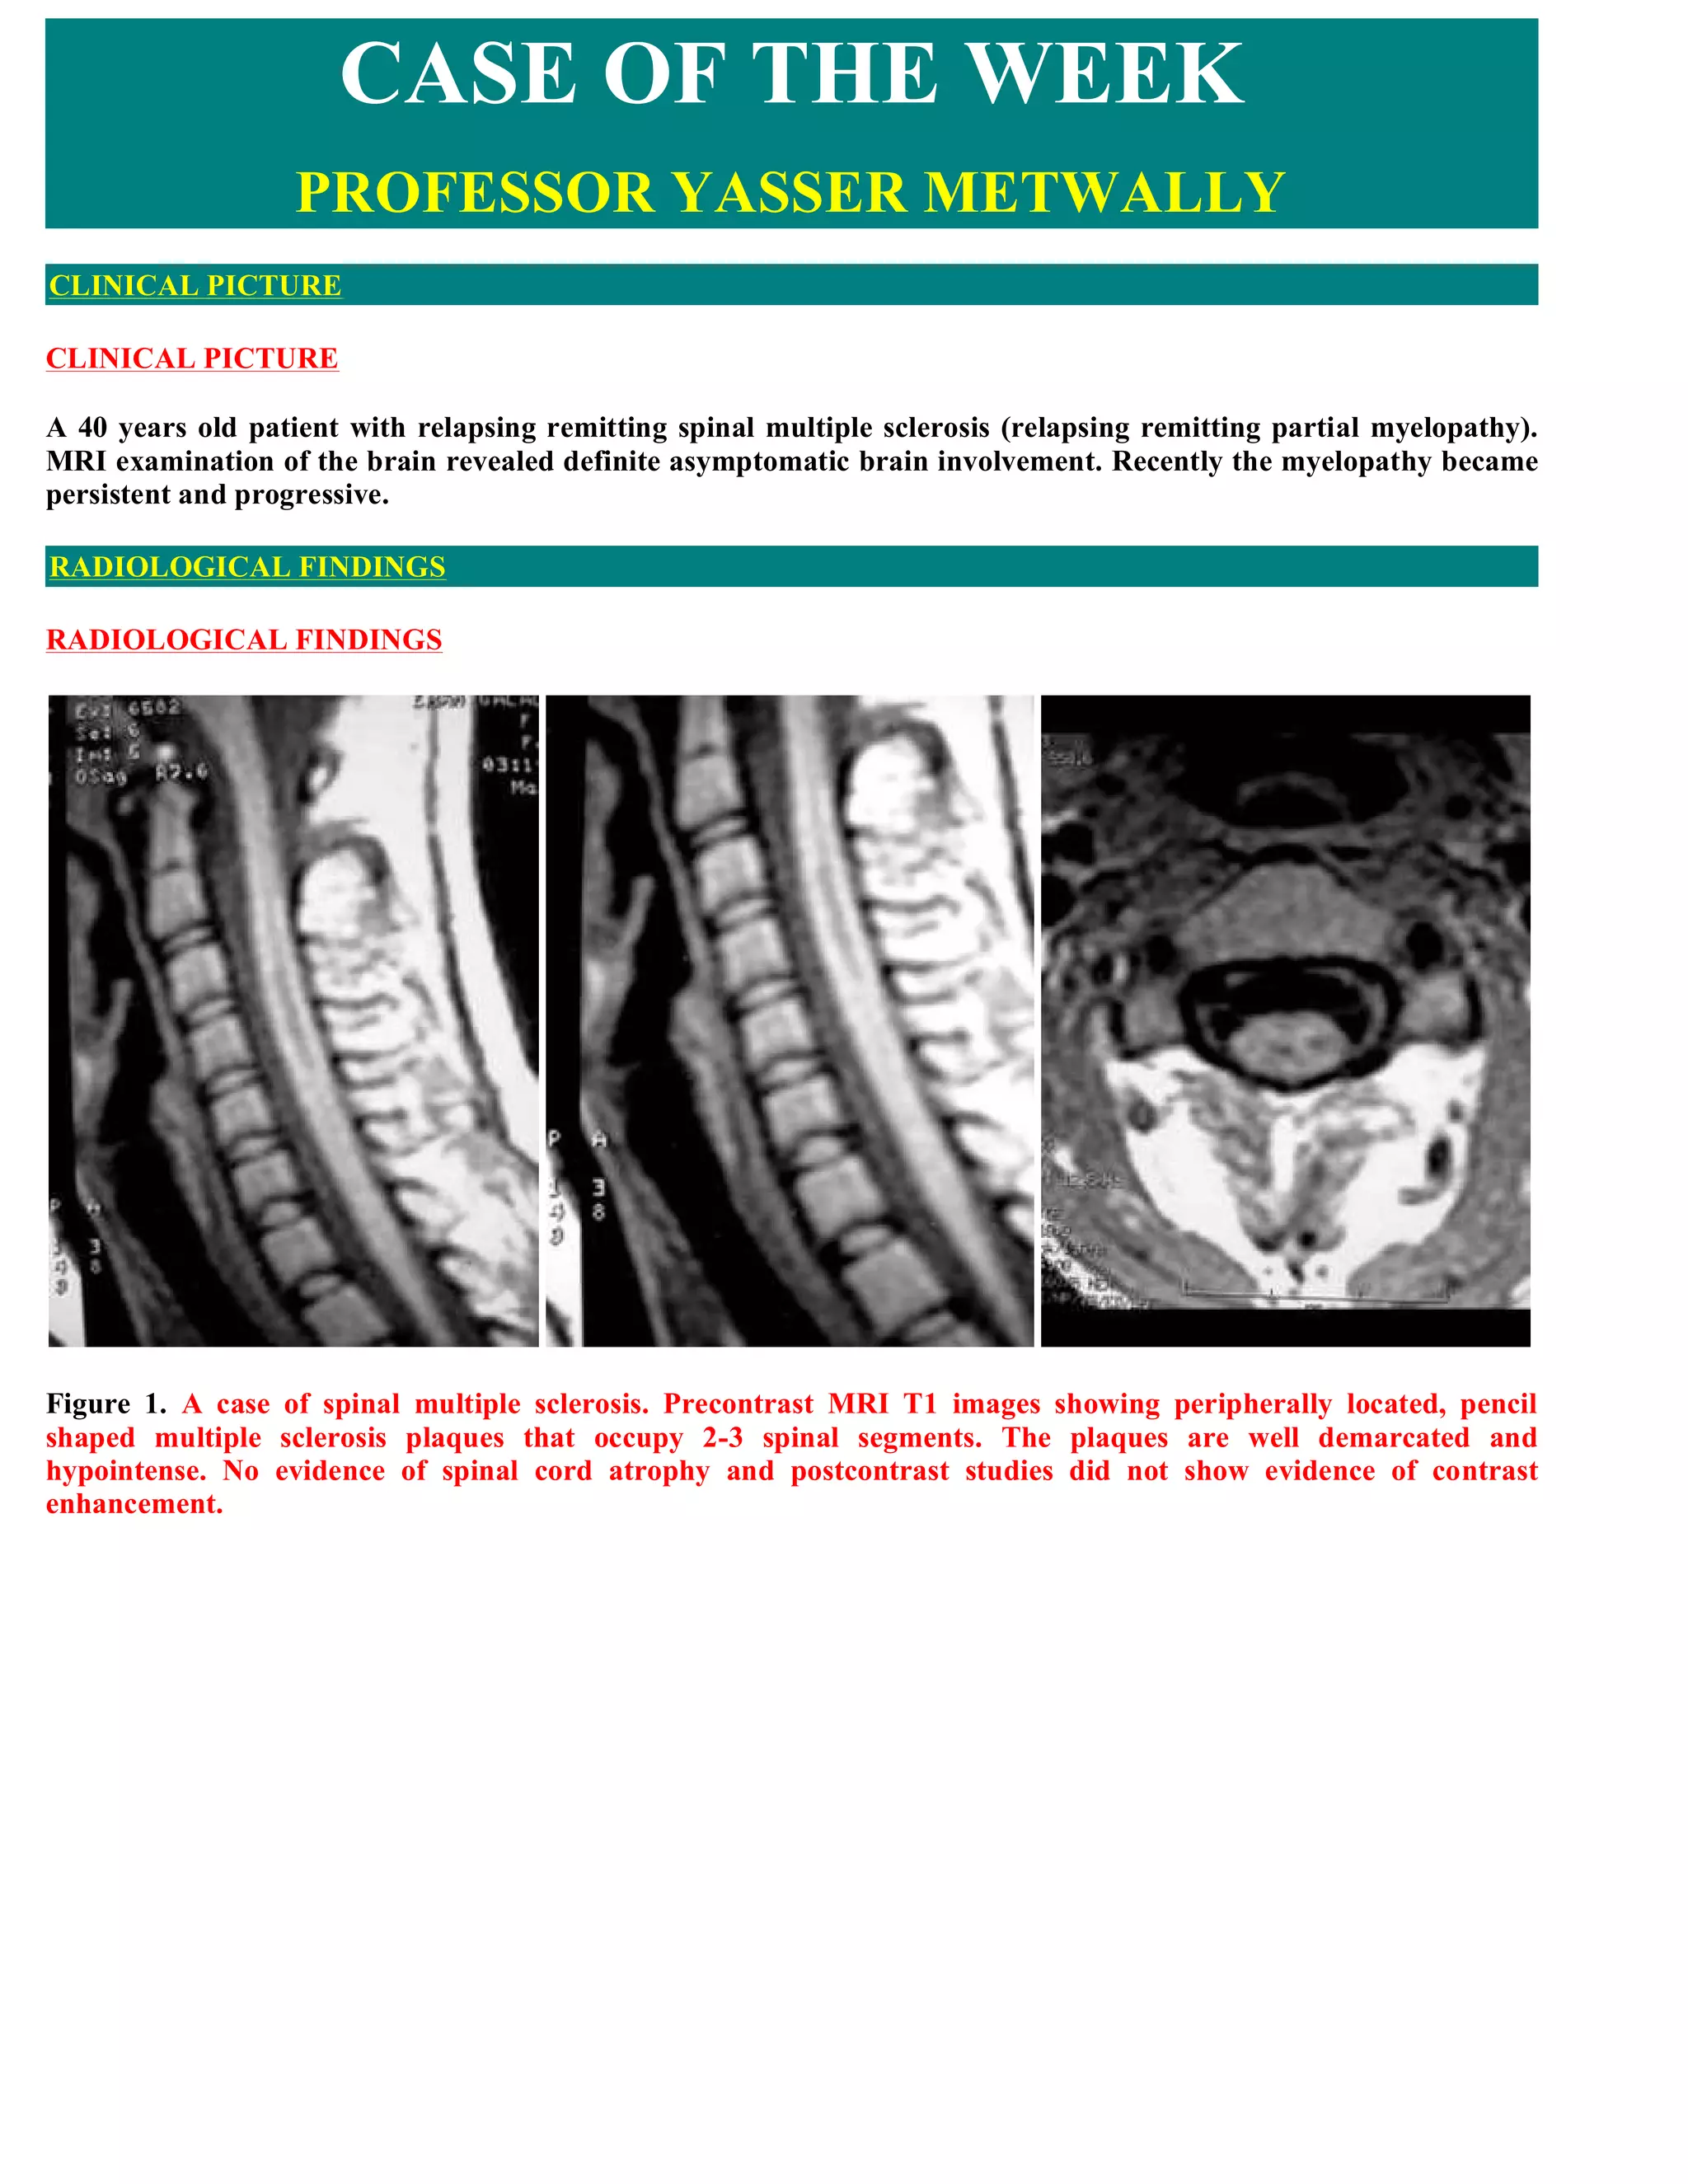

This document discusses a case of spinal multiple sclerosis in a 40-year-old patient. MRI images show well-defined pencil-shaped lesions occupying 2-3 spinal segments that are hypointense on T1-weighted images and hyperintense on T2-weighted images. Diffuse abnormalities are also seen as poorly demarcated hyperintense regions on T2-weighted images. The diagnosis is spinal multiple sclerosis. The document then discusses features of spinal MS lesions seen on MRI such as focal lesions, diffuse abnormalities, and spinal cord atrophy, and compares features of MS to other conditions like neuromyelitis optica.